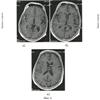

С экрана дисплея вычислили реальные величины линейных параметров на трех последовательных срезах, начиная с уровня базальных ганглиев, таламуса и выше. На уровне базальных ядер таламуса определили максимальную ширину сильвиевых борозд справа (20 мм) на фиг.2а и слева (14 мм) на фиг.2а; на уровне визуализации сосудистых сплетений желудочков головного мозга – ширину задних рогов боковых желудочков справа (15 мм) на фиг.2б и слева (12 мм) на фиг.2б и максимальное расстояние между внутренними пластинками костей черепа (150 мм) на фиг.2б; на уровне центральных частей боковых желудочков – минимальную ширину правого (14 мм) на фиг.2в и левого (15 мм) на фиг.2в тел боковых желудочков. Дополнительно рассчитали суммарный когнитивный индекс по предложенной формуле: СКИ=(20+14+15+12+14+15)/150=0,6. Сопоставили вычисленный индекс, равный 0,6, с его критическим значением 0,44. Вычисленный индекс выше значения 0,44, значит прогнозируем развитие постинсультной деменции. И действительно, на 21-ые сутки болезни осмотрен психиатром в связи с расстройствами памяти и мышления, затруднениями в выполнении навыков самообслуживания при регрессе неврологической симптоматики до рефлекторного центрального правостороннего гемипареза. Заключение психиатра: признаки сосудистой деменции с грубым нарушением самообслуживания.